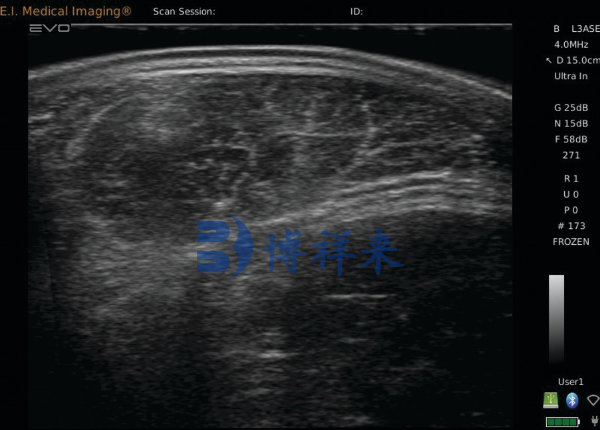

牛用B超,通常是指专为牛只设计的超声波诊断设备,主要通过超声波扫描获取牛体内的图像。这些图像可以实时展示肉牛的肌肉层、脂肪厚度、子宫状况等重要生理信息,帮助养殖者和育种专家做出科学的育种决策。

吉彩网 牛用B超可以精确测定肉牛的脂肪层厚度和肌肉层结构,尤其是在育肥牛的选育过程中,脂肪层和肌肉发育是影响肉质的重要因素。通过实时扫描,育种人员可以评估牛只的肉质潜力,选择出那些脂肪分布合理、肌肉发达的个体,从而提高肉牛的育种价值。

吉彩网 在肉牛育种过程中,牛用B超的应用不仅限于单一的肉质评估,它还可以帮助育种专家判断种牛的繁殖能力。例如,通过B超技术,育种专家能够实时监控母牛的卵巢和子宫状态,判断其是否适合配种。这一信息对于优化种牛选择、提高繁殖成功率具有重要意义。